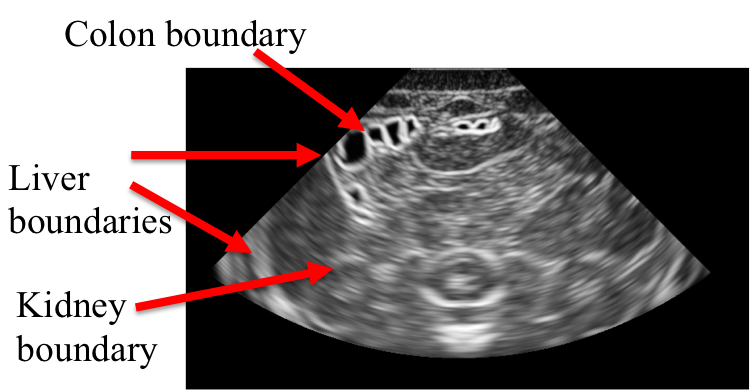

The medical ultrasound (US) is receiving increased attention despite the fast progress in other, higer resolution imaging modalities. This is due to several facts such as being the safest, the most cost efficient and the most portable medical imaging modality. The challenge in US imaging is that the images are noisy, free-hand slices (2D cross-sections) of the 3D body and furthermore the images are dependent not only on the US device parameters (such as transducer type, the operating frequency, gain, etc.) but also on user actions (such as the pressure applied to the body surface, the amount of gel used, etc.). Hence, even before diagnostic reading of US scans, the ultrasonographers must have been trained on 3D navigation within the body to be able to recognize the anatomical structures in these 2D noisy images.

The MUSE project aims at developing a real-time, true simulation of US images from 3D virtual patient models built using real volumetric medical image data. The current project involves:

- True and Real-Time US Image Simulation from Volumetric Data